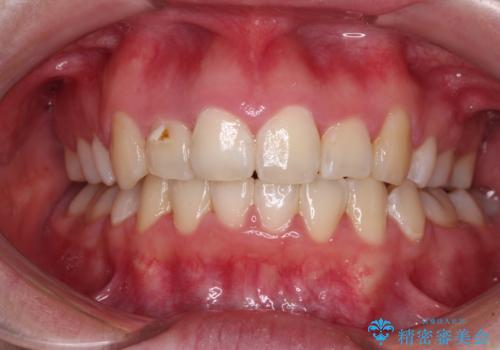

骨格的なズレをカムフラージュ 抜歯矯正で咬み合わせを改善

- 骨格的な咬み合わせのズレ、前歯のデコボコとクロスバイトを気にして来院された患者様です。

口元の突出感が若干あり口が閉じにくく、デコボコが強いため、上下左右の小臼歯計4歯を抜歯し、ワイヤー装置による矯正治療を行うこととしました。

また、舌の突出癖が強く、下顎前歯が前方に押し広げられる可能性が高いため、舌癖の改善を継続的に行うよう指示しました。